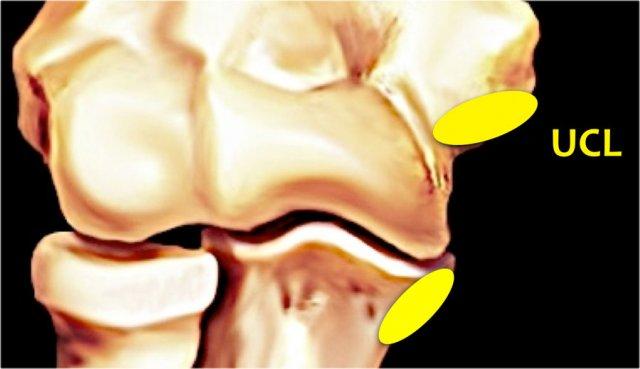

Ulnar Collateral Ligament

Dây chằng bên trụ (UCL) nằm ở phía trong và có ba thành phần.

Bó trước là thành phần chắc chắn nhất và là cấu trúc hạn chế chính chống lại lực valgus.

Trên MR, đây là cấu trúc quan trọng nhất.

Bó sau bám tận theo hình nan quạt vào mỏm khuỷu.

Nó tạo thành sàn của ống khuỷu.

Bó ngang chạy từ mỏm khuỷu đến mỏm khuỷu, vì vậy nó không có nhiều chức năng.

Dây chằng bên trụ (UCL) (màu vàng) xuất phát từ mặt dưới của mỏm trên lồi cầu trong, ngay bên dưới nguyên ủy của gân cơ gấp chung.

Nó bám vào một mấu nhỏ ở phía trong của mỏm vẹt, được gọi là củ sublime.